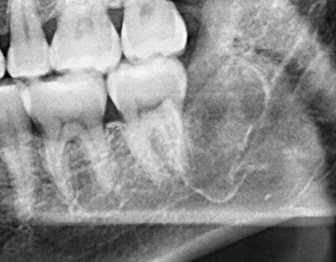

為了健保患者拔智齒的安全,遠離唇麻、舌麻、口鼻竇炎、大出血...等併發症,

☆本院特別巨資增設 ”千萬級3D AI透視電腦斷層”,並配合“成骨膠原蛋白”施作 (上述兩項目前健保無給付),讓您遠離神經傷害、口鼻竇(炎)相通...等併發症,除健保之外,難免會有避免併發症風險的自費項目,網路上經常會有看到智齒拔完後唇麻、舌麻、口鼻竇相通等併發症,在本院嚴格自我要求下,此類併發症在本院幾乎趨近於零。

(兩條紅線中間黑色區域即為神經管)

外面拔完時常術後唇麻舌麻,本院發生趨近於零